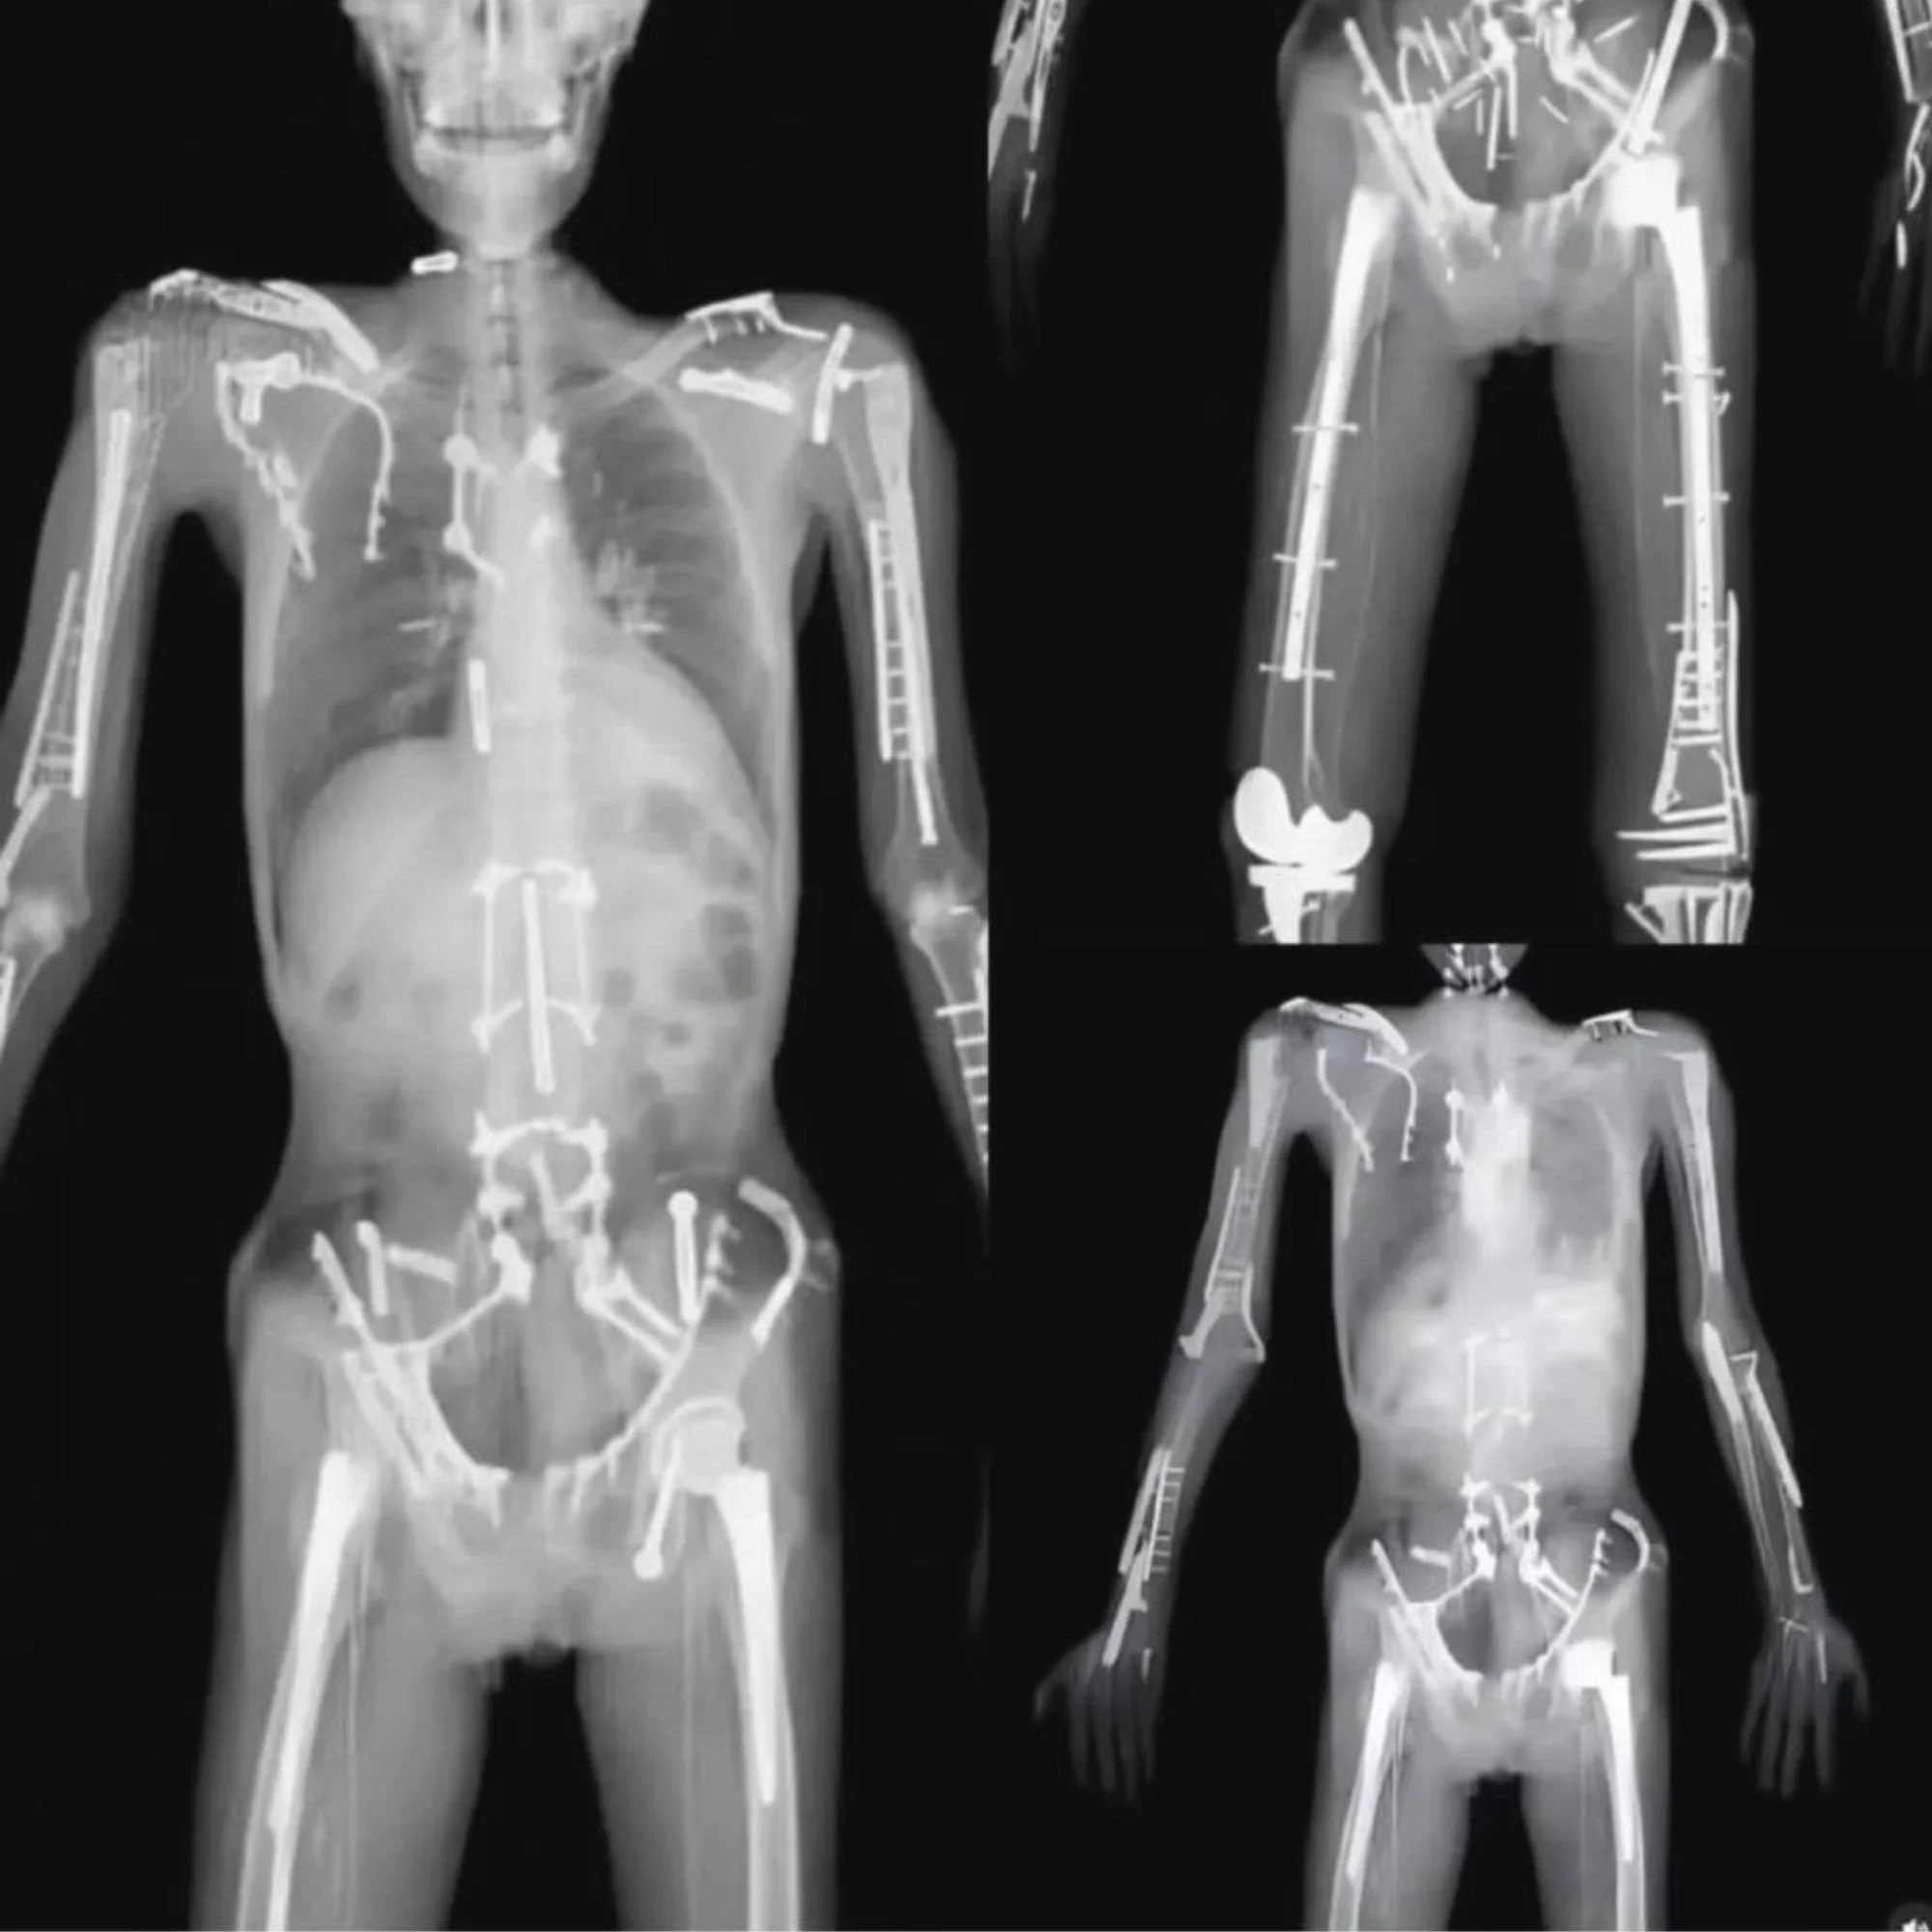

X-ray images showing the skeletal structure of three human bodies with pronounced medical implants and hardware, including metal rods, screws, and plates, in a black background.

Imagine receiving a chiropractic adjustment without your doctor knowing you have metal hardware, previous surgical changes, or structural differences in your spine.

The Gonstead Method emphasizes precision and safety. X-rays help guide specific spinal adjustments by providing a clear understanding of each patient’s unique anatomy.